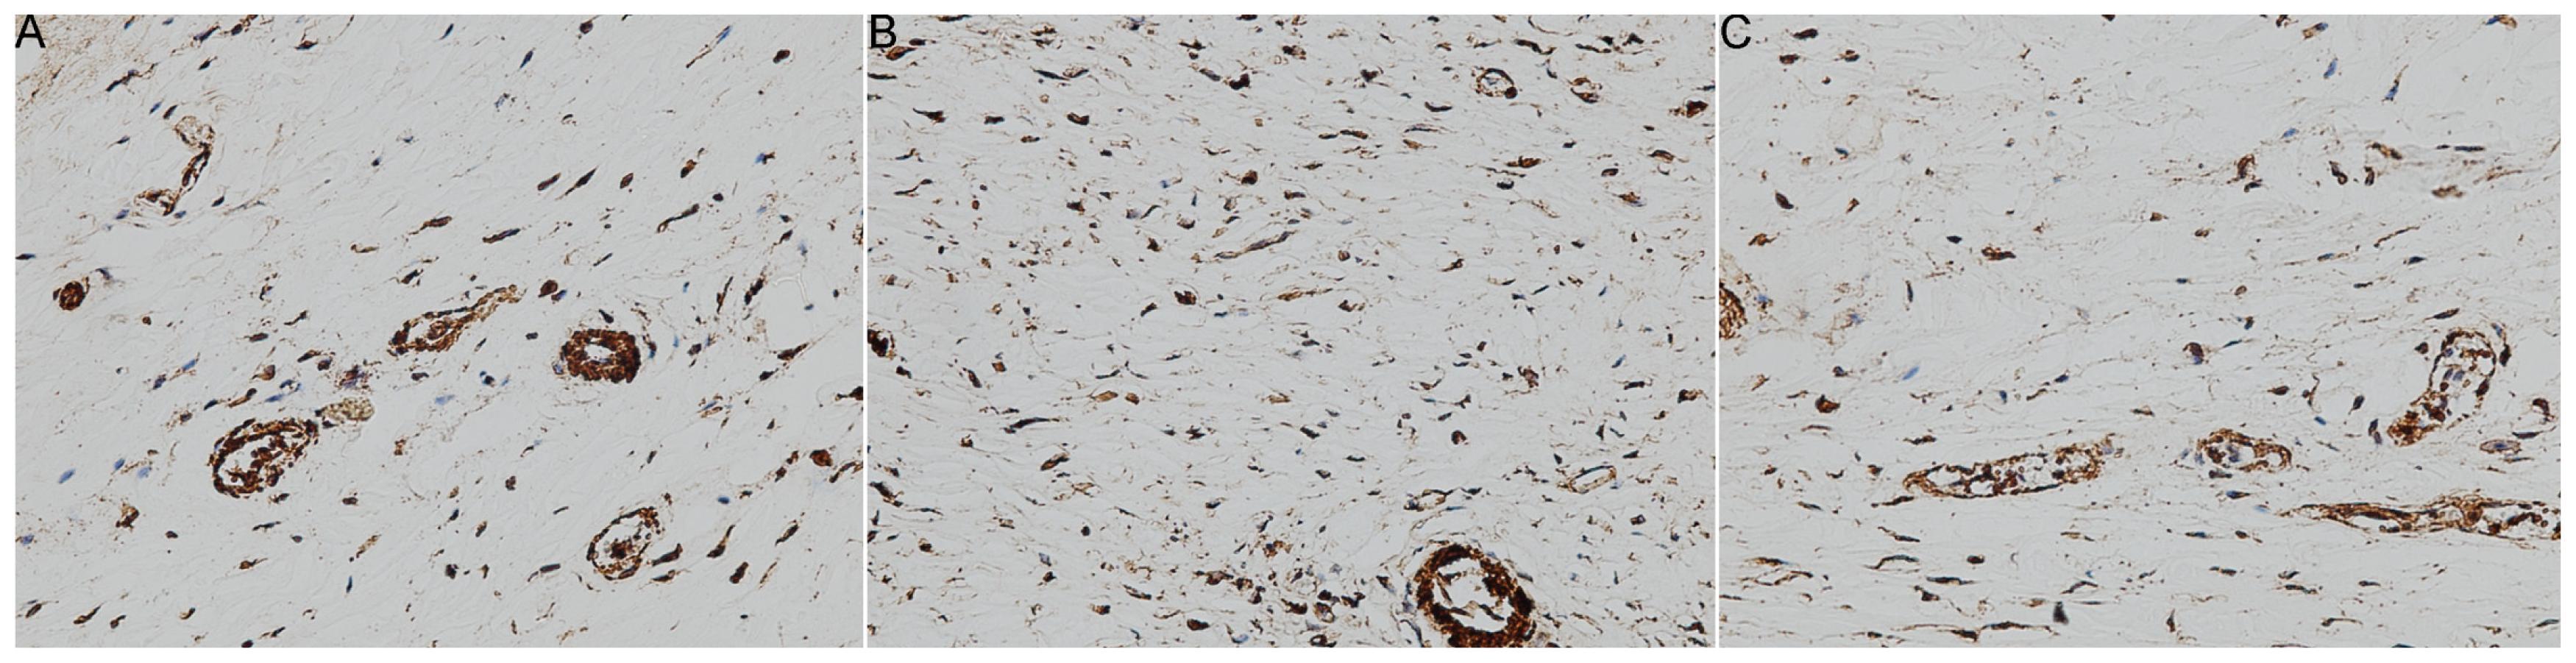

2. Results and Discussion

3.6. Immunohistochemistry